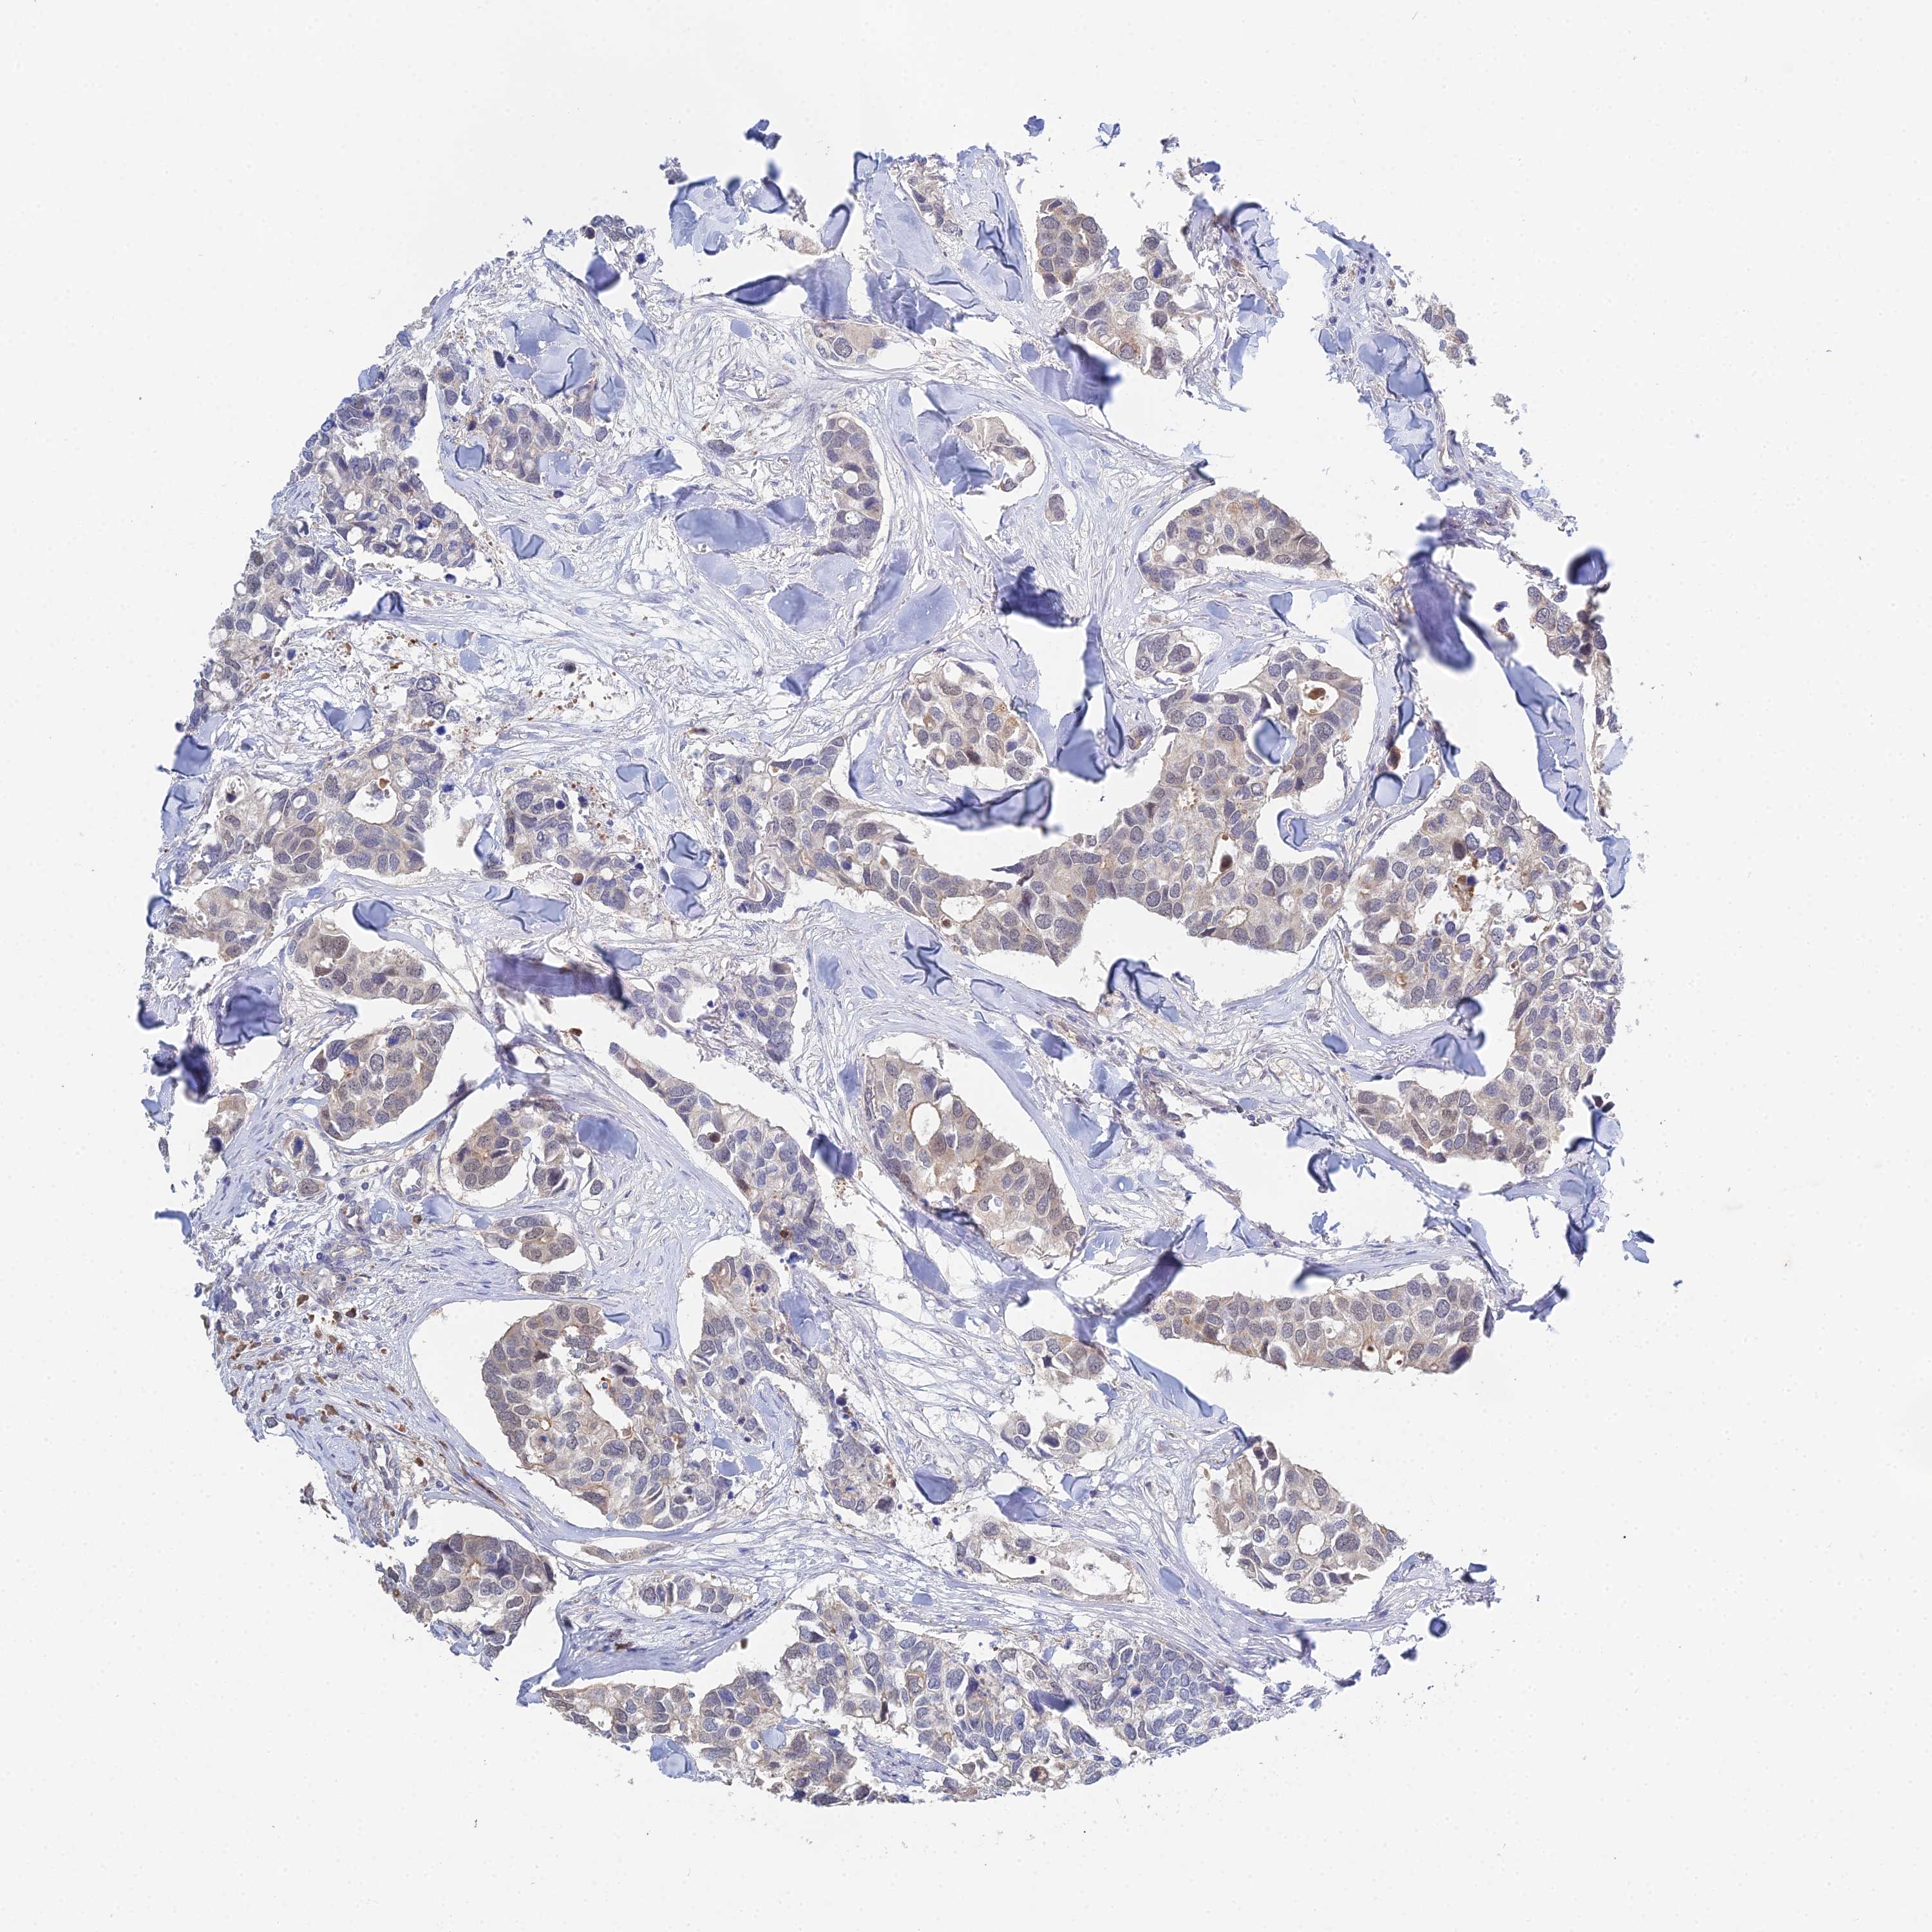

CANCER BREAST CANCER Show tissue menu

BRCA TCGA BRCA VALIDATION PROTEIN EXPRESSION

Breast cancer

Breast invasive carcinoma